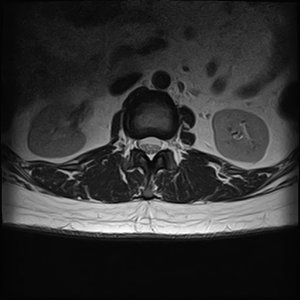

Заключение МРТ:

МР-признаки дегенеративно-дистрофичных изменений поперечного отдела хребта, секвестрированная экструзия диска L3-L4, пролапсы дисков L4-L5, L5-S1, Стеноз вертебрального канала на уровне L4-L5, L5-S1, выпрямленный поперечный лордоз.

Сама расшифровка:

Высота тел хрящей не снижена. Перихондрально в теле L5 есть признаки жировой дегенерации. В крайних отделах хрящей, большей частью по ветролатентным поверхностям, видны костные разростания-остеофиты. На уровне нижнегрудного, нижне поясничного сегментов наблюдается деформация, наружение целосности замыкающих пластинок тел хрящей.

Диск L3-L4 снижен по высоте, выступает дорсально, парамедианно в лево до 8,5 мм, фораминально в лево до 2,7 мм, в правл до 1,5 мм, целостность фиброзного кольца нарушена, межхребтовые отверстия сужены, дуральный мешок и нервные корешки компремованные, сагитальный розмер вертебр. канала до 12 мм.

Диск L4-L5 снижен по высоте, выступает дорсально с двухсторонней латеризацией до 4 мм, фораминально в обе стороны до 2,5 мм, межхребтовои отверстия сужены, сагитальный розмер вертебр. канала до 16 мм.

Диск L5-S1 снижен по высоте, выступает дорсально с двухсторонней латеризацией большей частью парамедианно в лево до 4 мм, фораминально в лево до 3 мм, вправо до 2 мм, межхребтовои отверстия сужены, сагитальный розмер вертебр. канала до 12 мм.

Спинной мозг не изменен по толщине и интнсивности МР-сигнала, конус на уровне L1.